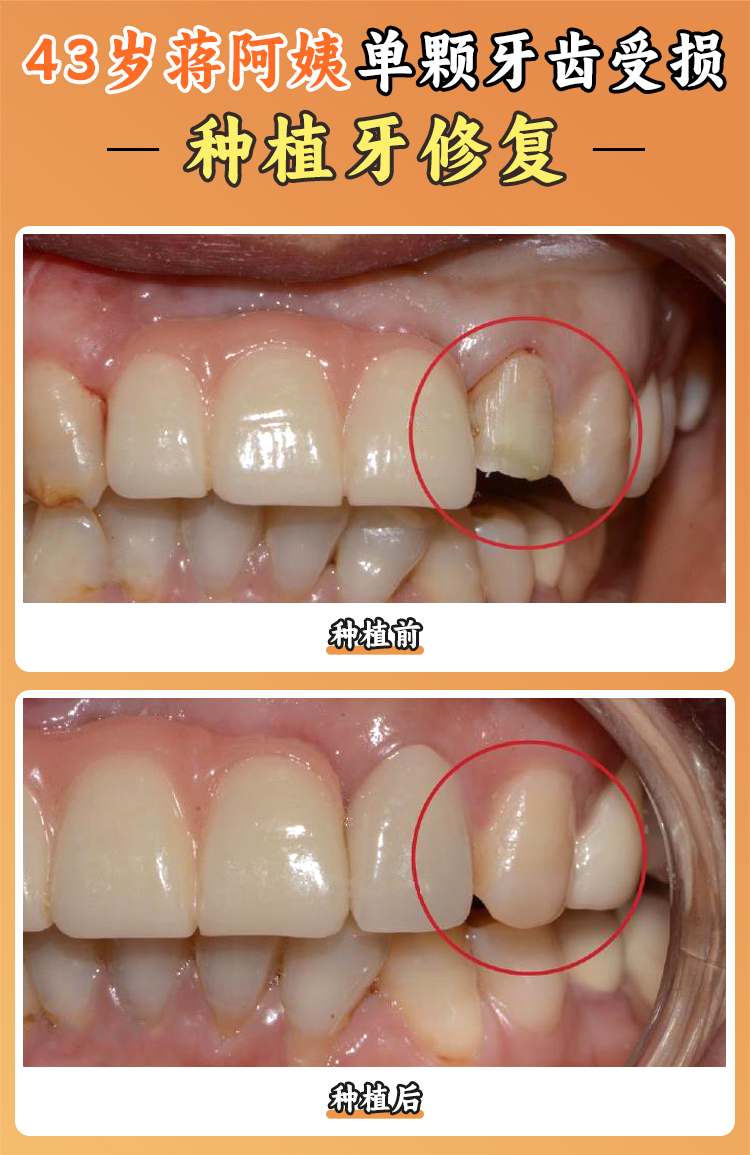

韓亞超醫(yī)生是一位從業(yè)多年的全科醫(yī)生,他是中老年口碑王。其專精領(lǐng)域?yàn)槲?chuàng)拔智齒(10分鐘搞定)、牙周序列治療,并且他的技術(shù)特色是殘根保留修復(fù),能夠?yàn)榛颊呤∠路N牙錢?;颊邔?duì)他的評(píng)價(jià)非常高,認(rèn)為他在微創(chuàng)拔智齒方面技術(shù)嫻熟,手術(shù)時(shí)間短,術(shù)后復(fù)原比較快,深受患者喜愛。